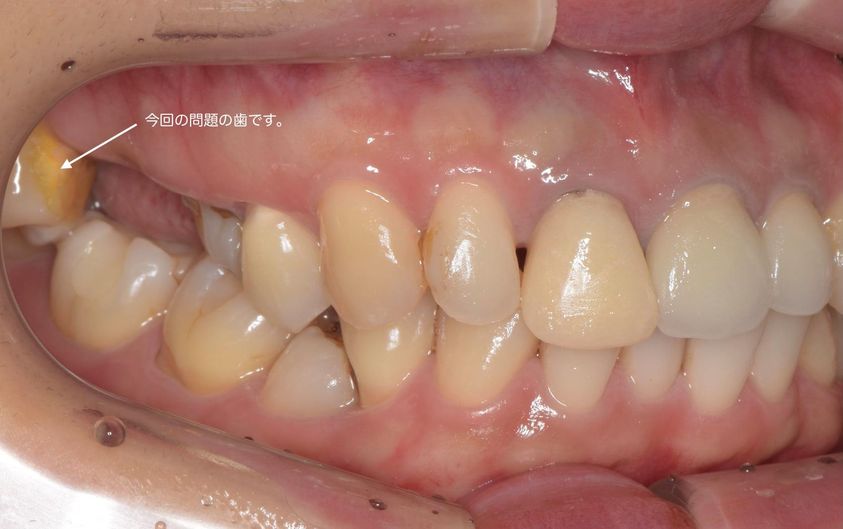

この写真は名取歯科医院で抜歯診断をした患者さんです。名取歯科医院では、歯をできるだけ削らず、神経を保存し、天然歯を残すことを一番に考えています。何故、抜歯という診断をしたのかお話しします。

この状態を改善するために名取歯科医院では、根本治療として矯正治療を提案しましたが、患者さんは矯正治療をお望みではありませんでした。そのためデンタルドック(歯の人間ドック)の診査診断から、この歯の抜歯提案を行いました。この治療方針は患者さんから了承を頂いていましたが、患者さんのご都合で抜歯は他院という事になりました。

もちろん、この歯だけを見れば抜くべきではないと判断も間違ってはいないかも知れません。しかし今までの複数回に及ぶ前歯部セラミックの破損、顎に現状抱えている痛み症状、他の歯に対する治療の安定性といったお口全体(一口腔内)を見た場合、名取歯科医院では抜歯判断をすることがあります。